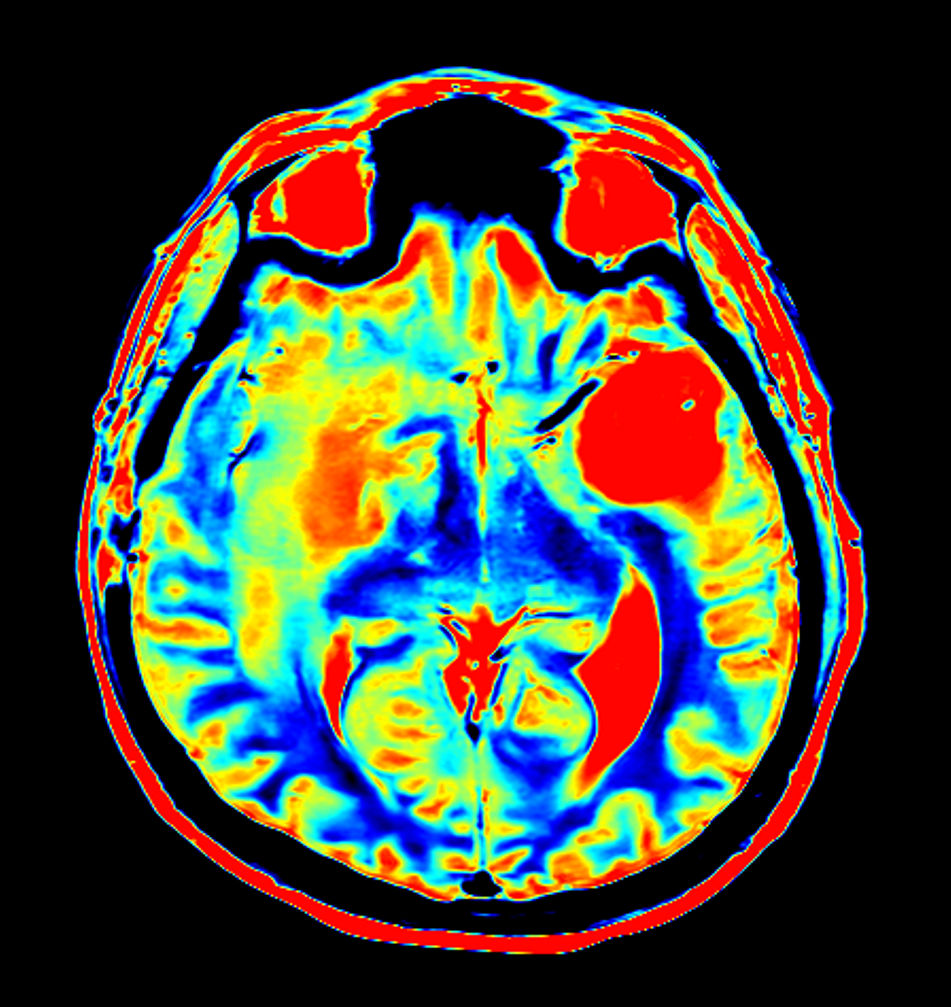

Axial T2* Perfusion (NI)